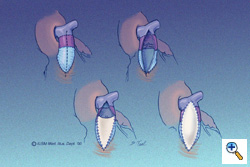

For the patient who has had a previous RVOT conduit that has become stenotic, the PTFE monocusp may be used as an alternative to valve or conduit replacement. This illustration shows a vertical incision through the extent of the previously placed valved conduit. The previously placed valve is partially excised. A hinge point is selected for the monocusp, usually at the mid-portion of the old conduit. The monocusp valve is constructed as shown in the lower left panel. Finally, a 0.4-mm thickness PTFE cardiovascular patch is used, again in a teardrop configuration, to create a roof over the monocusp patch. Sizing of the monocusp is essentially the same as with other repairs; the material must have adequate length and width in order to have sufficient surface area contact against the posterior wall.

For the patient who has had a previous RVOT conduit that has become stenotic, the PTFE monocusp may be used as an alternative to valve or conduit replacement. This illustration shows a vertical incision through the extent of the previously placed valved conduit. The previously placed valve is partially excised. A hinge point is selected for the monocusp, usually at the mid-portion of the old conduit. The monocusp valve is constructed as shown in the lower left panel. Finally, a 0.4-mm thickness PTFE cardiovascular patch is used, again in a teardrop configuration, to create a roof over the monocusp patch. Sizing of the monocusp is essentially the same as with other repairs; the material must have adequate length and width in order to have sufficient surface area contact against the posterior wall.